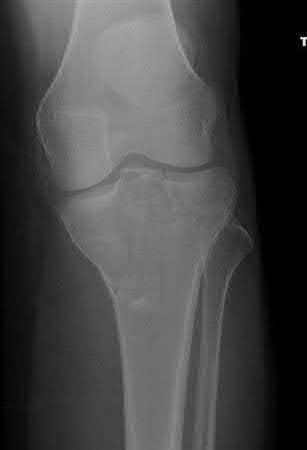

A 38-year-old male suffers the injury shown in Figure A. During operative fixation, free osteoarticular fragments are encountered and reconstruction of these pieces is attempted. Postoperatively, which of the following will have the most beneficial effect on the healing potential of the surviving chondrocytes within these reconstructed articular segments?

Figure A demonstrates a comminuted tibial plateau fracture with significant intra-articular involvement. Basic science evidence has demonstrated that post-operative gentle compressive loading may have a positive impact on articular cartilage healing; however, excessive shear loading may be detrimental.

Irrgang et al provide guidelines for rehabilitation following surgical management of articular cartilage lesions of the knee. They state that after articular cartilage repair, exercises to enhance muscle function must be done in a manner which minimizes shear loading of the joint surfaces in the area of the lesion. The authors also discuss the benefits of gentle compressive loading and motion of the joint, and its positive effects on chondrocyte nutrition.

Furthermore, they recommend a period of protected weight bearing as often being necessary, and that this should be followed by progressive loading of the joint.